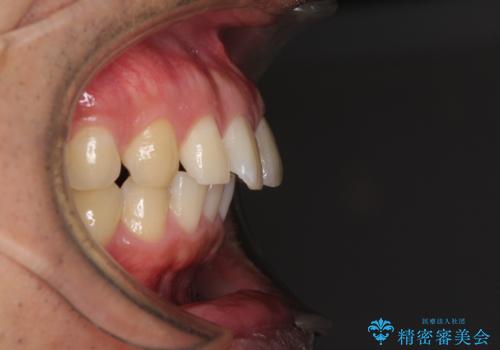

- 上顎前歯の突出感とすきっ歯を気にして来院された患者様です。

奥歯の咬み合わせを見ると、下顎に対して上顎が前方に位置していたため、補助装置により上顎歯列全体を後方に移動させ、その後インビザラインにて歯列全体を整えることとしました。